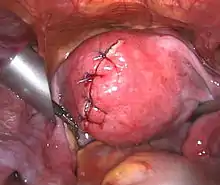

![]() | |

| Uterine fibroids as seen during laparoscopic surgery | |